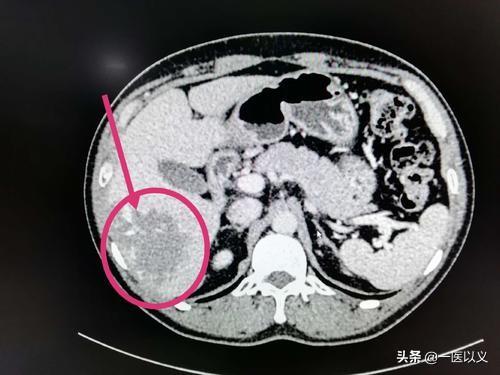

- 一方、肝CTは肝血管腫の数と大きさをより明瞭に示すことができ、肝超音波検査よりも優れた結果を示す。肝超音波検査で肝血管腫が発見された患者に対しては、さらに肝CT検査を行い、血管腫の数、大きさ、位置などを明らかにすることができる。

上の画像は肝血管腫のCT画像で、右葉に低密度の陰影があり、境界が明瞭で、増強後に端から中心に向かって漸増する。